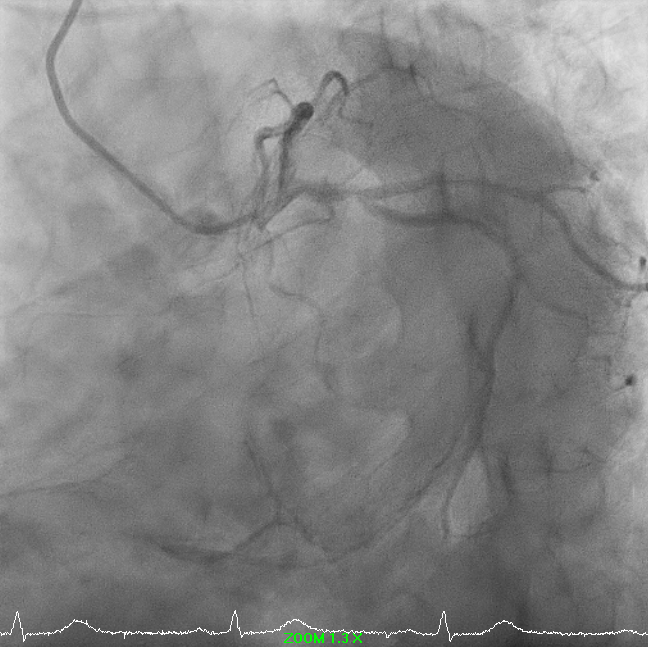

Right-dominant system. Proximal LAD shows 50% moderate calcified disease. Proximal LCx has 50% stenosis with severe calcification. RCA demonstrates severe diffuse proximal–mid 70% stenosis with moderate calcification and distal severe ISR-CTO with heavy calcification and minimal antegrade flow. Impression: Complex RCA ISR-CTO as culprit with moderate pLAD/pLCx disease.

8.avi

9.avi

11.avi